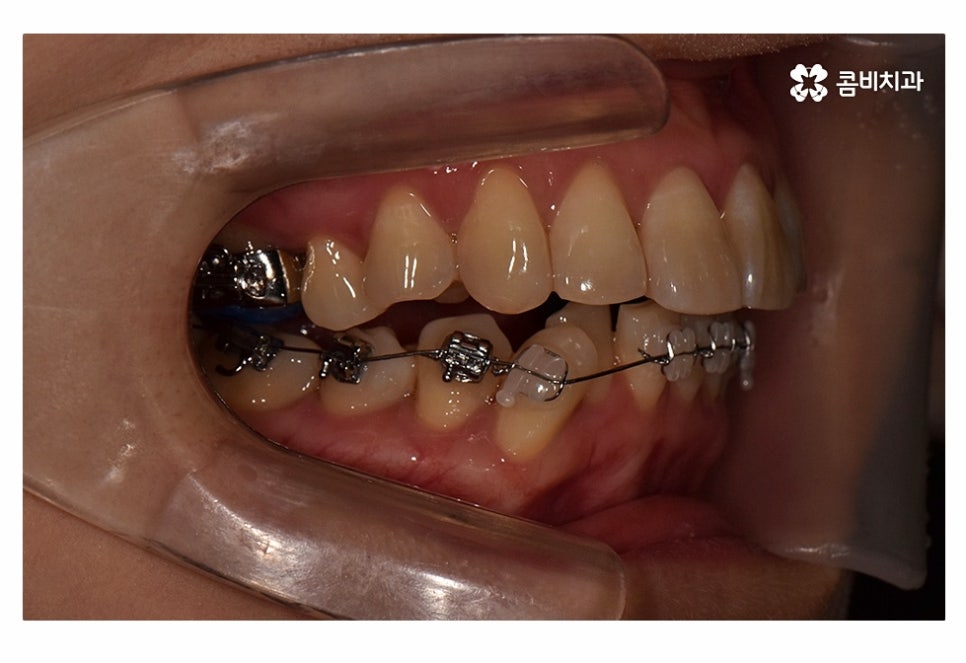

오늘 보실 교정 사례 역시도 윗니는 치아 설측교정으로

진행이 되고 아랫니는 일반적인 순측교정으로 진행되었으며

이러한 치아교정 방법을 콤비교정이라고 부르고 있어요.

위 사진에서 보시는 것과 같이 윗니의 경우 치아설측교정으로

진행이 되고 있기 때문에 교정 장치가 눈에 띄지 않고 있어요.